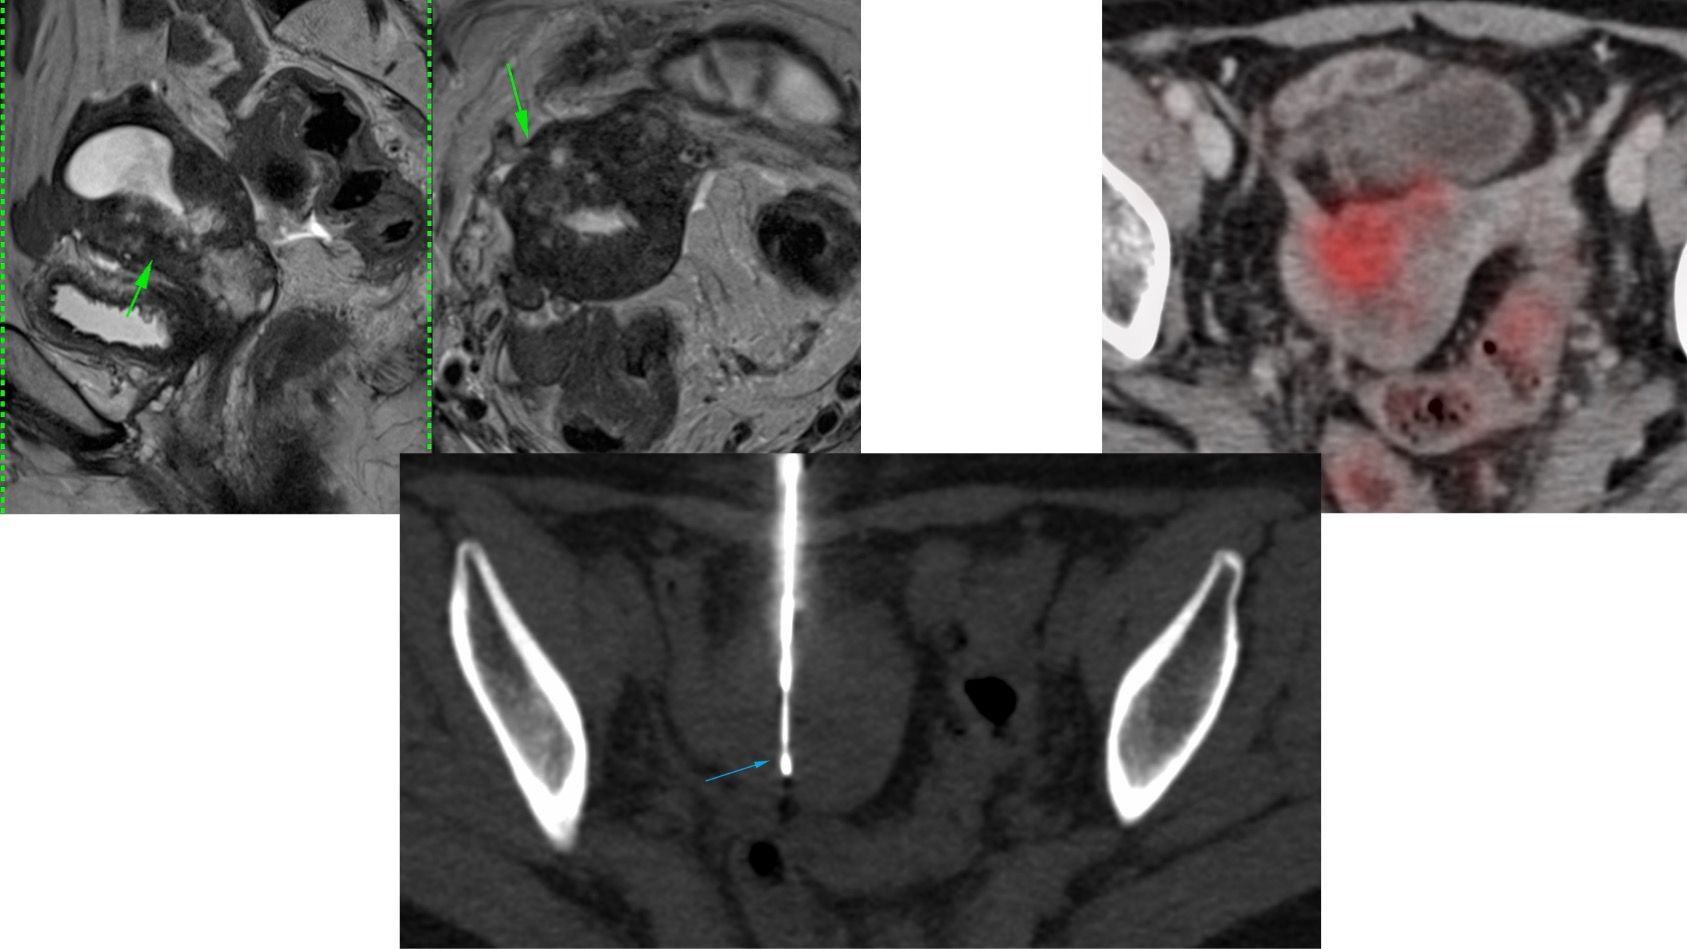

Case 126: Intra-Uterine Mass Biopsy

Bhavin Jankharia - 25 June 2023